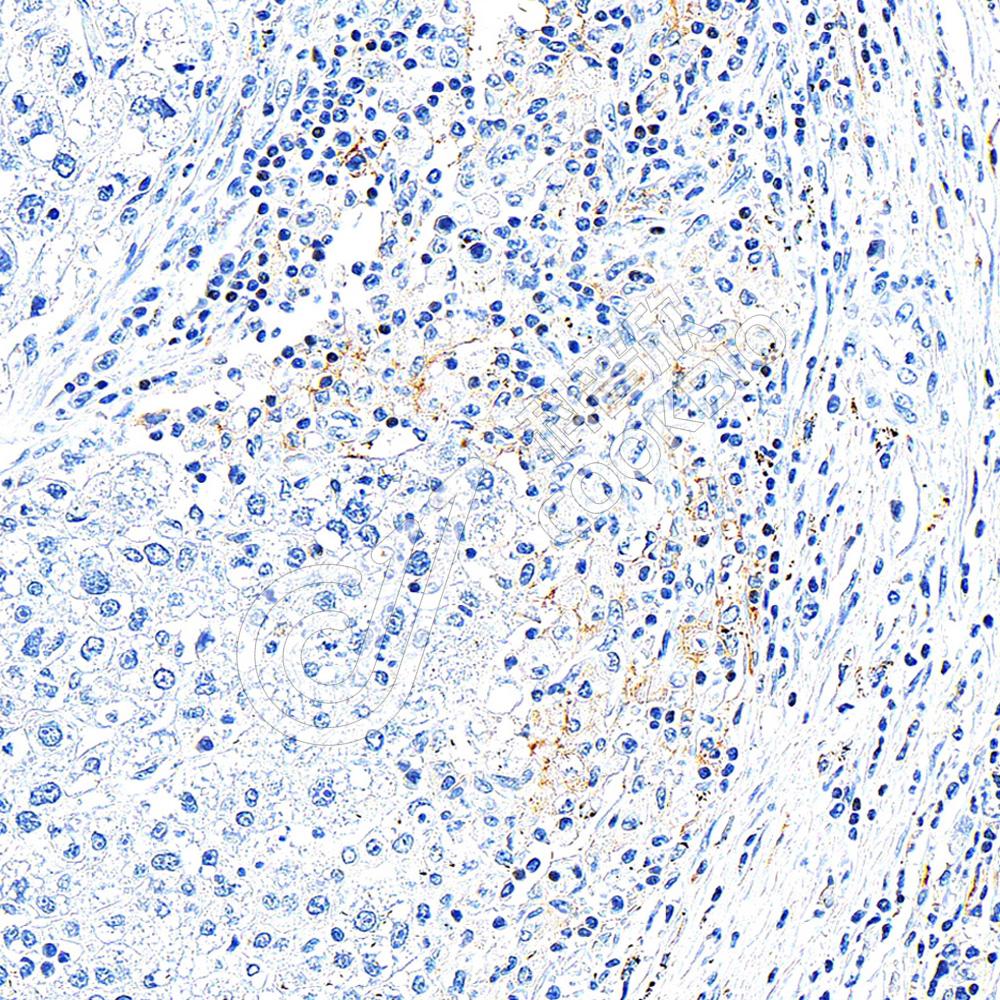

IHC检测CD11c蛋白(货号 K1347070).

样品: 人肝癌, 4%多聚甲醛 (货号KSG1101) 固定12-24小时.

抗原修复: 柠檬酸抗原修复液(干粉, pH 6.0) (KSG1201), 98℃, 20分钟.

—抗: 1: 800稀释, 4℃ 孵育过夜.

二抗: S-vision免疫组化多聚二抗(山羊抗兔),即用型 (货号KB3906), 室温孵育20分钟.